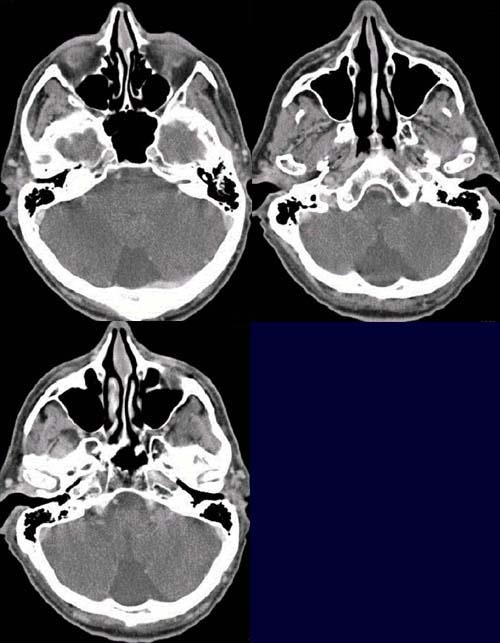

CCT nativ (ohne Kontrastmittel).

Weichteildichte

Verschattung

des Epitympanum und knöcherne

Destruktion des Innenohres auf der linken Seite (oberes Bild).

Ebenfalls weichteildichte Verschattung des Mesotympanum links ohne Destruktion

der Gehörknöchelchenkette (mittleren Bild). In der koronaren Rekonstruktion

ist die knöcherne Destruktion

des Tegmen tympani zu erkennen (mittleres Bild)

sowie das Cholesteatom

im Meso- und Epitympanum (unteres Bild).